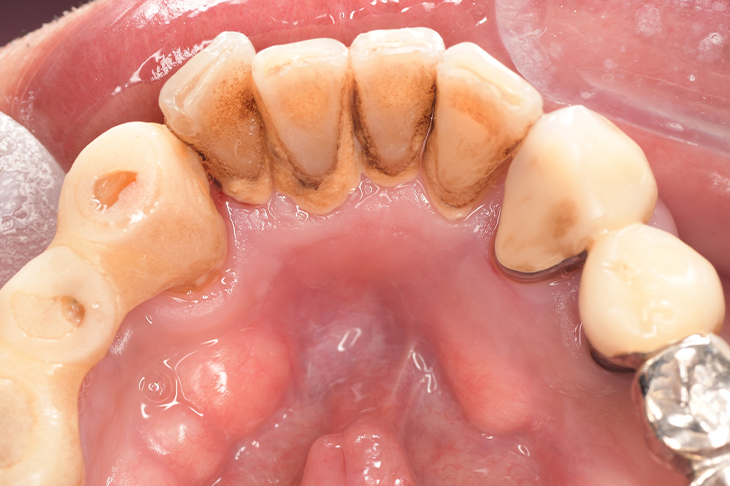

CASE 12

Before

| 年齢・性別 | 46歳・男性 |

| 主訴 | 歯石をとりたい |

| 治療内容 | スケーリング |

| 治療期間 | 30分 |

| 治療費 | 1,500円(保険診療) |

| リスク・副作用 | 知覚過敏、歯肉退縮、出血 |

| 治療方針 |

歯肉縁上歯石を除去して、次回から歯肉縁下歯石を除去します。 その後も定期的にクリーニングを行い、メインテナンスしていきます。 |